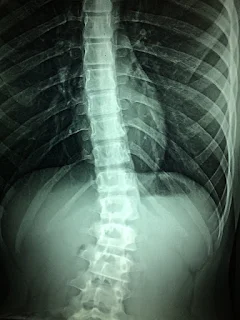

Other than feeling pain from the site of the tumor, other symptoms include nerve compression that makes the limbs feel week or sore, increased back pain when laying or sitting down, and chills and night sweats when sleeping. Sometimes there is no pain at all. The tumors are diagnosed by an evaluation of the spine. Starting with a classic physical examination, your neurologist will check your spine any tenderness, internal or external sweeping, and measure the strength of your limbs and back. Further examination that can be done includes testing your senses such as pain and pressure sensitivities, motor strength, and your natural reflexes. Sometimes x-rays are necessary to diagnose the size and type of tumor, and a further MRI will be ordered to examine if it is localized or spreading.